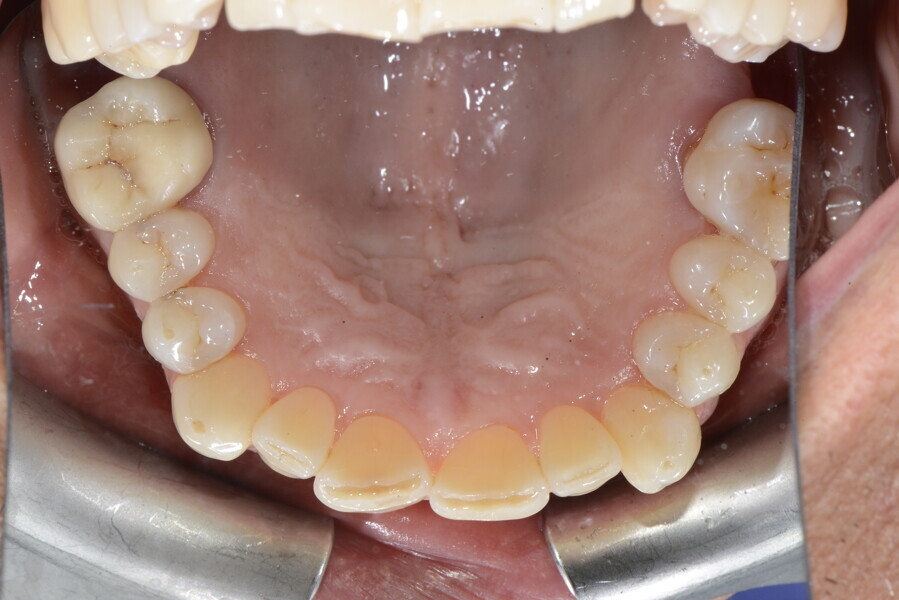

The 58-year-old patient wished to improve his oral aesthetics and function, complaining of mobility of the posterior teeth and wear of the anterior teeth. After data collection, a very complex situation was identified (Figs. 11–13):

1. severe periodontitis with poor prognosis of some teeth;

2. anterior crossbite;

3. severe wear mainly of the anterior teeth and compensatory eruption;38

4. atypical swallowing and lower posture of the tongue at rest;

5. masticatory dysfunction during the mastication test; and

6. no significant signs of temporomandibular disorder.